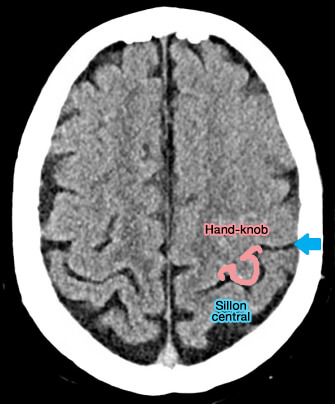

La représentation de la main dans l'aire motrice primaire est principalement localisée dans un segment spécifique du gyrus précentral, appelé " hand-knob ", i.e. de knob, bouton, en raison de son renflement visible en forme d'oméga ou d'epsilon dans les images IRM axiales (Anatomo-functional characterisation of the human “hand-knob”: A direct electrophysiological study 2019).

• Il existe des des asymétries anatomiques, i.e. droitier et gaucher, suggérant en outre le développement des mains dans la formation du sillon central, étant donné que le " hand-knob " est la partie centrale du sulcus replié dans le gyrus enfoui (The effect of handedness on the shape of the central sulcus 2012).